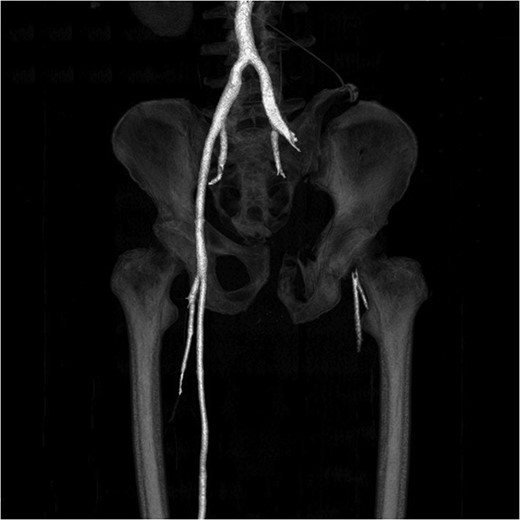

A 55-year-old male arrived at the ER, a large tree having fallen across his pelvis. The patient was hypotensive at the scene. He received over 1500 ml of crystalloid in route to the emergency room. Upon arrival to St. Mary’s Medical Center, the patient had a systolic pressure of 70. His heart rate was in the 130 s. The patient was awake and alert. A left subclavian central line was placed and he was transfused with two units of O-blood. The patient’s abdomen was soft and nontender. The patient had blood at his meatus. The patient’s pelvis was tender to palpation. His left leg was cold, mottled and pulseless. There was no femoral pulse on the left side. The chest x-ray was normal, however, the pelvis film revealed extreme widening and displacement of the symphysis pubis (Fig. 1). A bedsheet was wrapped around the patient’s pelvis and another two units of O-packed red blood cells were administered. Additionally, he was given four units of fresh frozen plasma. The patient was started on norepinephrine to control his persistent hypotension. His systolic blood pressure rose into the mid-90s and the patient was taken to the CT scanner. The CT scan revealed that the patient had an acute occlusion of his left iliac artery, as well as a large left iliac wing fracture with a massive associated hematoma. A right iliac wing fracture was located near the sacroiliac joint. There was pubic diastasis, as well as a left superior rami fracture with a modest associated hematoma. There was no extravasation of dye (Figs 2 and 3). The patient was taken directly to the operating room because he was developing significant abdominal distention in the face of continued hypotension. Anesthesiologists placed a second large-bore central line for fluid resuscitation. An exploratory laparotomy was performed, revealing an intraperitoneal bladder rupture. The patient was bleeding freely from his pelvic hematoma. Multiple attempts were made to pack the pelvis tightly with laparotomy pads, but efforts were unsuccessful. Because of the distorted anatomy obtaining proximal and distal control of the iliacs was extremely difficult. The patient suffered massive retroperitoneal venous bleeding, which we were unable to control. The patient exsanguinated on the operating room table; despite having received over 30 units of packed red blood cells, 30 units of fresh frozen plasma, several 10 packs of platelets, cryoprecipitate and factor VII A.